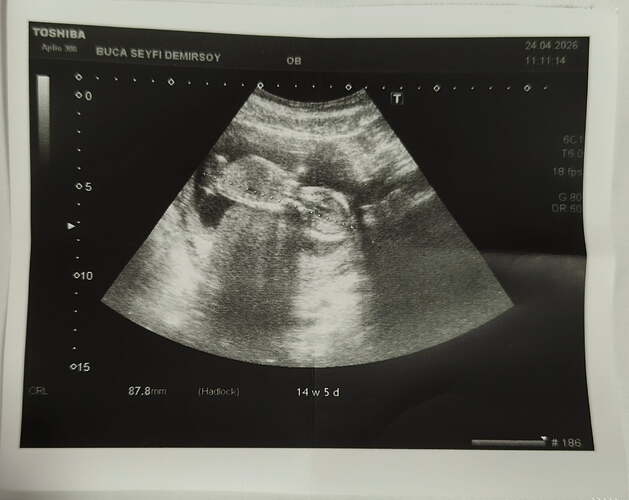

Hayırlısı inşallah cnm 2 haftaya öğrencem bakalım![]()

Prenses gibi canım bacak arasından bir çıkıntı yok

Kızzz olabiliiir